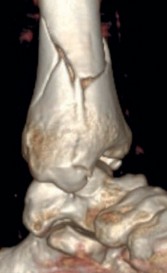

Fig 2.2-3a–h A CT scan with 3D reconstruction.

a–d Sagittal (a–b), coronal (c), and axial (d) images demonstrate displaced posterior, anterolateral, and medial fracture fragments resulting in intraarticular step and gap. The incongruent tibiotalar joint is best appreciated on the sagittal scan.

e–h The 3D reconstructed images show the external fracture anatomy and general alignment.